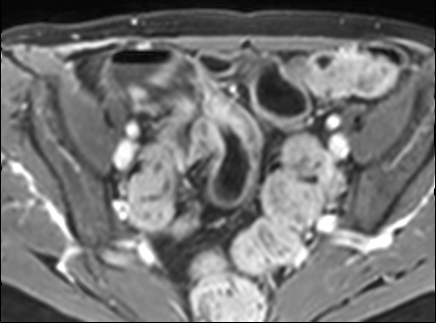

Đoạn hồi tràng cuối dày thành với ngấm thuốc mạnh trên hình ảnh T1W axial sau tiêm thuốc tương phản từ có fat-sat.